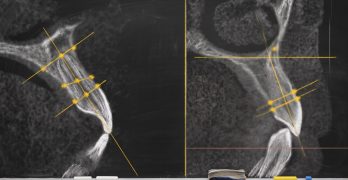

Caninos impactados: ¿Es hora de actualizar tu enfoque diagnóstico?

El artículo que compartimos hoy se llama Can Panoramic Radiography Reliably Detect Root Resorption From Impacted … [Leer más...] acerca de Caninos impactados: ¿Es hora de actualizar tu enfoque diagnóstico?